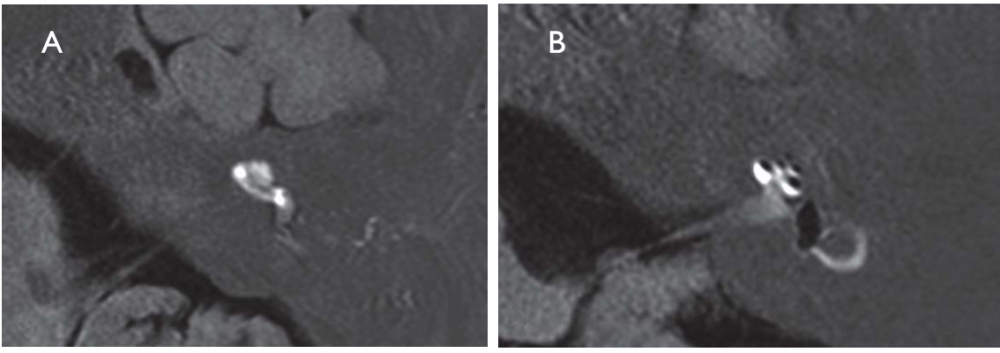

The pathognomonic histopathological finding is endolymphatic hydrops, which is evident on high resolution MRI of the petrosal bone after transtympanic injection of gadolinium (Figure 1). However, endolymphatic hydrops can be found in the saccule in 10% of normal individuals and in 40% of patients with greater than 45 dB SNHL without any vestibular symptoms2.

A. The labyrinth of a healthy control: The cochlea and semicircular canals are visualized.

B. The labyrinth of a patient with Menière's disease: the endolymphatic hydrops can be recognized by virtue of its lack of contrast medium uptake.

Redrawn from: Strupp M, Dieterich M, Brandt T. The treatment and natural course of peripheral and central vertigo. Dtsch Arztebl Int. 2013;110(29-30):505-15.